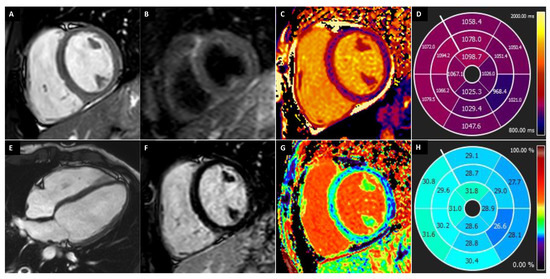

2.4.1. T1 Mapping

2.4.2. T2 Mapping

2.5. Extracellular Volume Fraction

| Mapping | Reduced (T1-T2) | Increased (T1) | Increased (T1-T2) | Increased (T1) | - | - | Increased (T1) |

| ECV | Reduced | Increased | Increased | - | - | - | Increased |